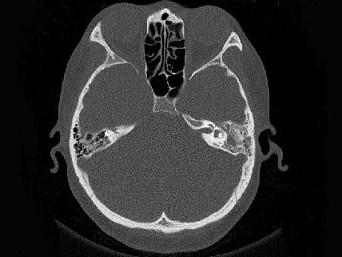

女,34岁,左耳鸣,听力下降两个月,PE:左外耳道有脓性分泌物,鼓膜充血水肿,左中耳腔内软组织影,CT检查如图,最可能诊断为 ( )